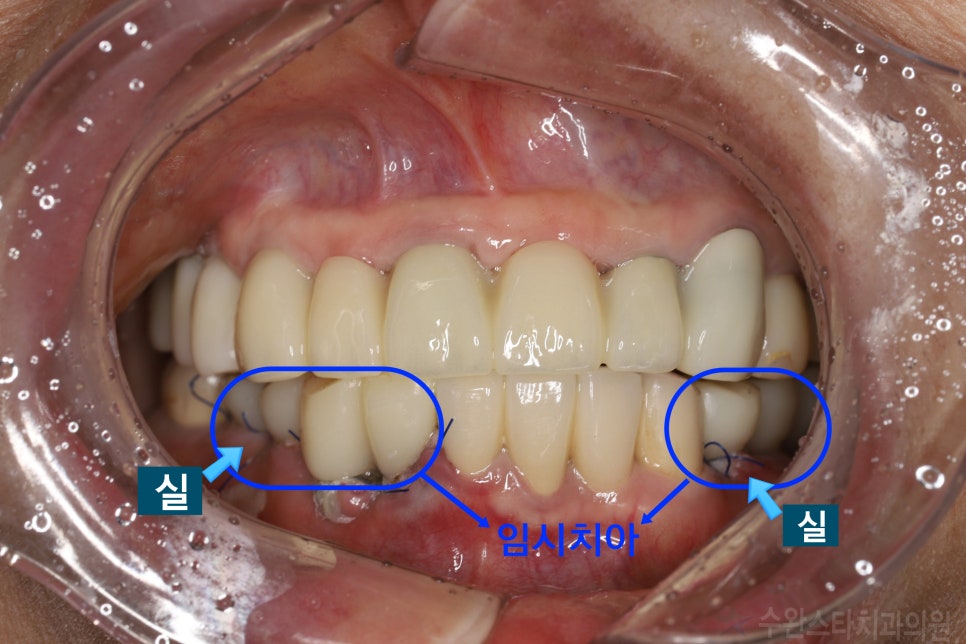

수술 후 3일 경과 (60대 여성, 2024.06)

실도 빼기 전인

수술 후 3일 만에

바로 씹을 수 있게

치아를 넣어드렸습니다.

임플란트 수술 전 / 수술 후 정면 (60대 여성, 2024.06)

실을 제거하기 전에

임시 치아를 넣으면

바로 씹는 것도 가능해지며

치아가 없는 상태로 인한

불편함을

최소화할 수 있습니다.